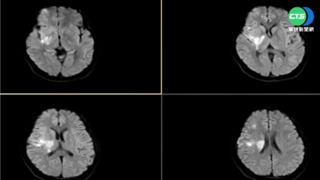

這般景象令人看了難過。亞瑟與利馬不僅頭骨相連、共有一部分大腦,還共用一條「輸送血液回心臟」的靜脈。這一天,他倆生命走到了關鍵時刻,巴西里約熱內盧醫院出動了100名醫護團隊,首次透過虛擬實境連線與英國的醫療團隊合作,準備替雙胞胎進行頭骨分割手術。連同這一次手術,兄弟倆共挨了7次刀。

除了要分割、重建回流心臟血液的靜脈,讓兩人都擁有各自的靜脈之外,最棘手的是兩人腦部部分相連,如何分割而不傷及腦部功能,是個大學問,英國與巴西醫療團隊透過虛擬實境合作,第7次進行了27小時馬拉松的手術,醫療團隊形容,手術重要性有如人類登陸火星。

手術結果,兩個小兄弟成功存活,至於腦部受損程度仍待評估。由於小兄弟倆不到4歲,未來腦部開發還有很大的空間,可以透過復健補強開發腦部功能。